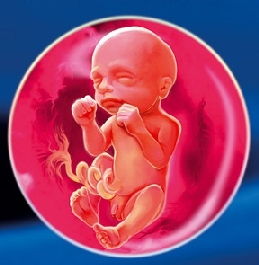

фото: 22 тиждень розвитку плода

Вага плоду на 22 тижні вагітності становить 430-500 г, а зріст сягає близько 28 сантиметрів.

Мозок дитини на цьому етапі вже майже сформувався: зростання його зупиняється, склад клітин мозку стає повноцінним і важить 100 г. У зв'язку з цим формуванням, рефлекси вдосконалюються і все ускладнюється: малюк на 22 тижні вагітності вже не просто смокче палець, але в його силах тепер нахилятися, рухатися вперед.

Активно розвиваються потові залози немовляти, розміри серця значно збільшуються. У кісткової тканини продовжує відкладатися кальцій. Одночасно, хребет повністю сформувався - він включає в себе всі хребці, міжхребцеві диски.На тілі дитини стають помітними Пушкова волоски, їх ще називають лануго. Вони утримують первородну змазку, яка покриває все тіло малюка.